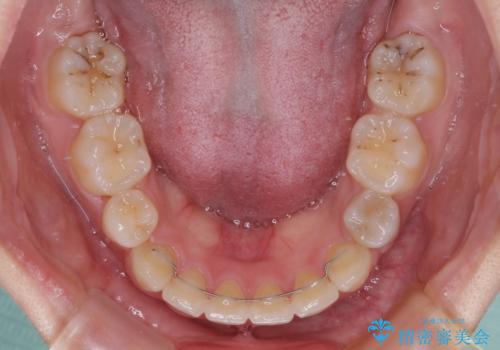

- メタルブラケット

上下ともに歯列が前方に突出していたため、上下左右の第一小臼歯4本を抜去する方針(既に上顎は抜歯されています)で、ワイヤー装置による矯正治療を行うこととしました。

舌の突出癖があり、咬合力も強かったため、治療期間は長くなることが懸念されましたが、舌のトレーニングをしっかりと行っていただいたこともあり、2年弱で治療を終えることができました。